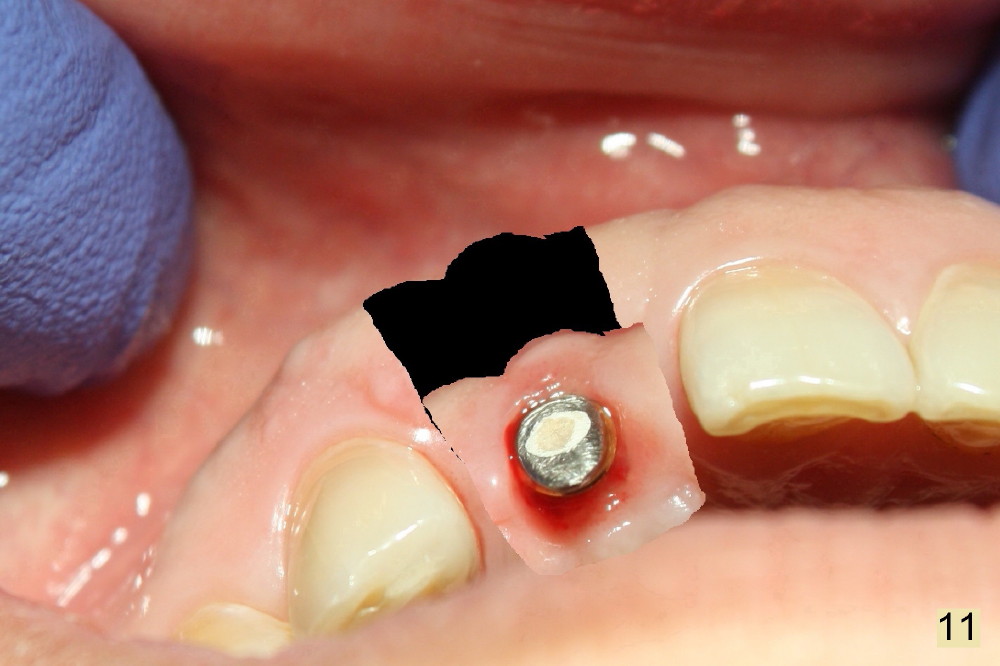

Fig.7,8 show the provisional 10 days and 1.5 months postop, respectively. When the provisional is removed, the implant/abutment is buccally malpostioned (Fig.9). It appears that segmental osteotomy is necessary. Fig.10 shows incision design. The implant and bone complex is to be moved to an ideal position (Fig.11,12). A block graft is inserted apically for internal fixation. An ortho wire is used for external fixation.